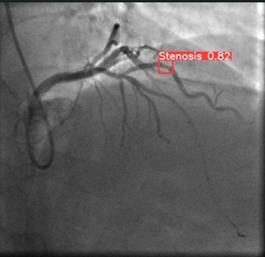

XCA is particularly beneficial in diagnosing coronary artery stenosis (CAS), a condition characterized by the narrowing of the coronary arteries due to plaque buildup [8]. The procedure involves inserting a catheter through the femoral artery into the heart, followed by the injection of contrast material to visualize the coronary vessels. Meanwhile, the pressures inside the heart are monitored, and its contractile function is tested by introducing contrast material into the left ventricle. Following the examination, 4-6 hours of bed rest are usually recommended. Typically, XCA provides high-resolution images, like the ones shown in Figure 1 [9], that allow physicians to detect stenotic areas in coronary arteries and evaluate their severity.

Figure 1. Coronary angiography images and areas of stenosis for a CAS patient [9]